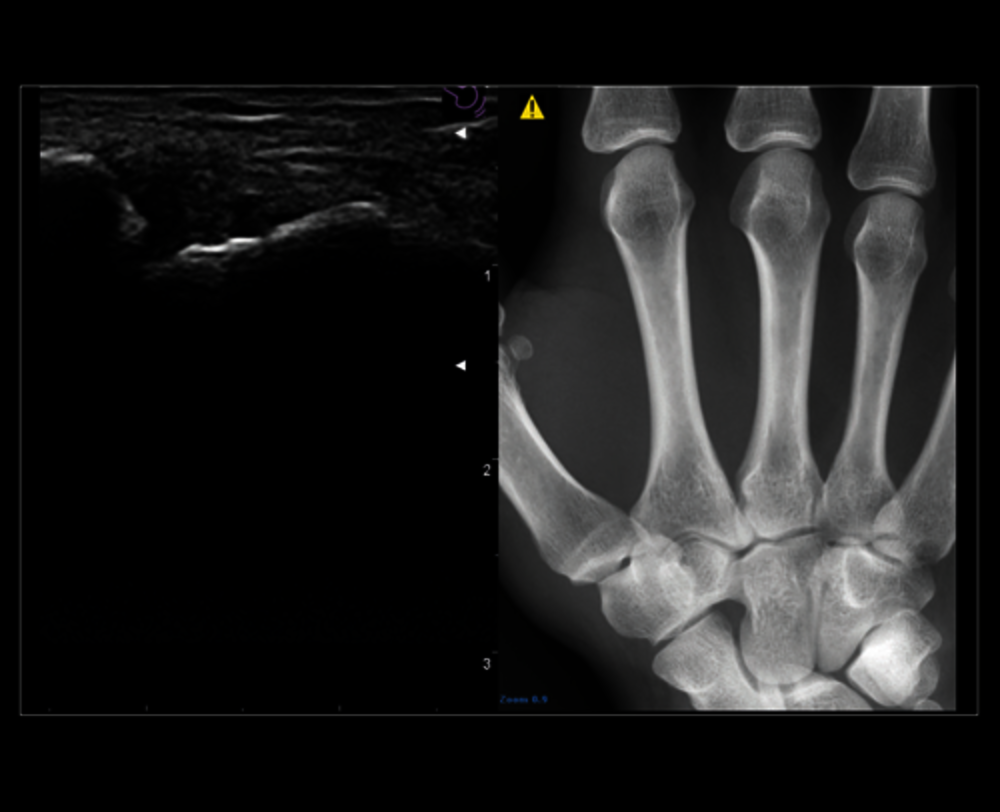

MSK zobrazení ramene

Výkonový Doppler v oblasti zánětu akutní polyartritidy se sondou 18 MHz

Zvýraznění jehly pro přesný intervenční postup

Sledujte v reálném čase druhou modalitu